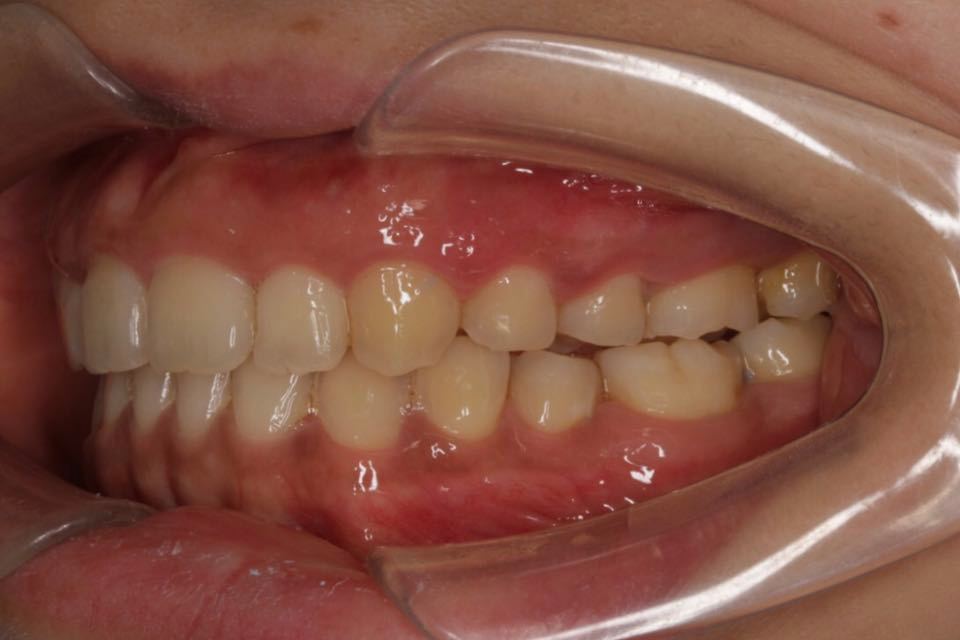

矫正前口内照:

口内:恒牙列,牙列拥挤(中度)。上下颌牙弓呈方圆型。左右对称。右侧磨牙近中性关系,左侧磨牙近中关系,右侧尖牙远中关系,左侧尖牙远牙中性关系。上颌中线偏右2mm,下中性居中。